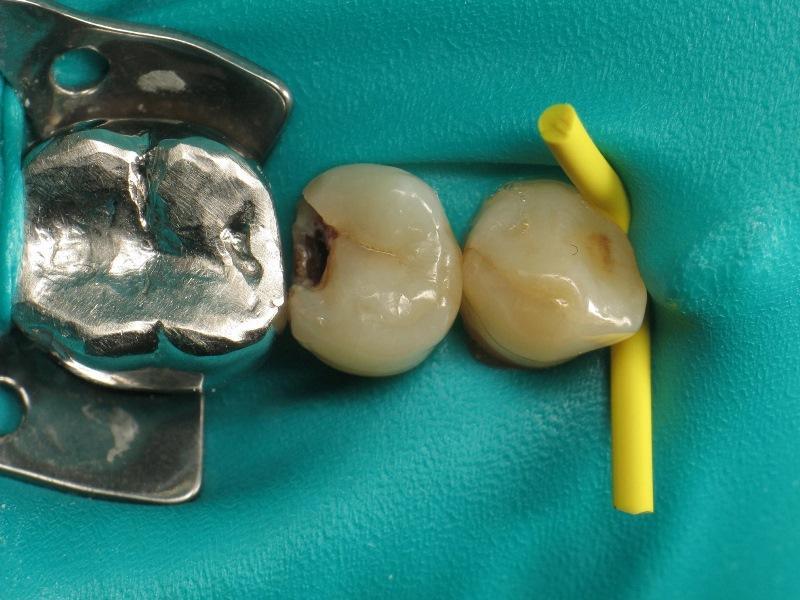

Фото 1. Премоляр с кариесом II класса.